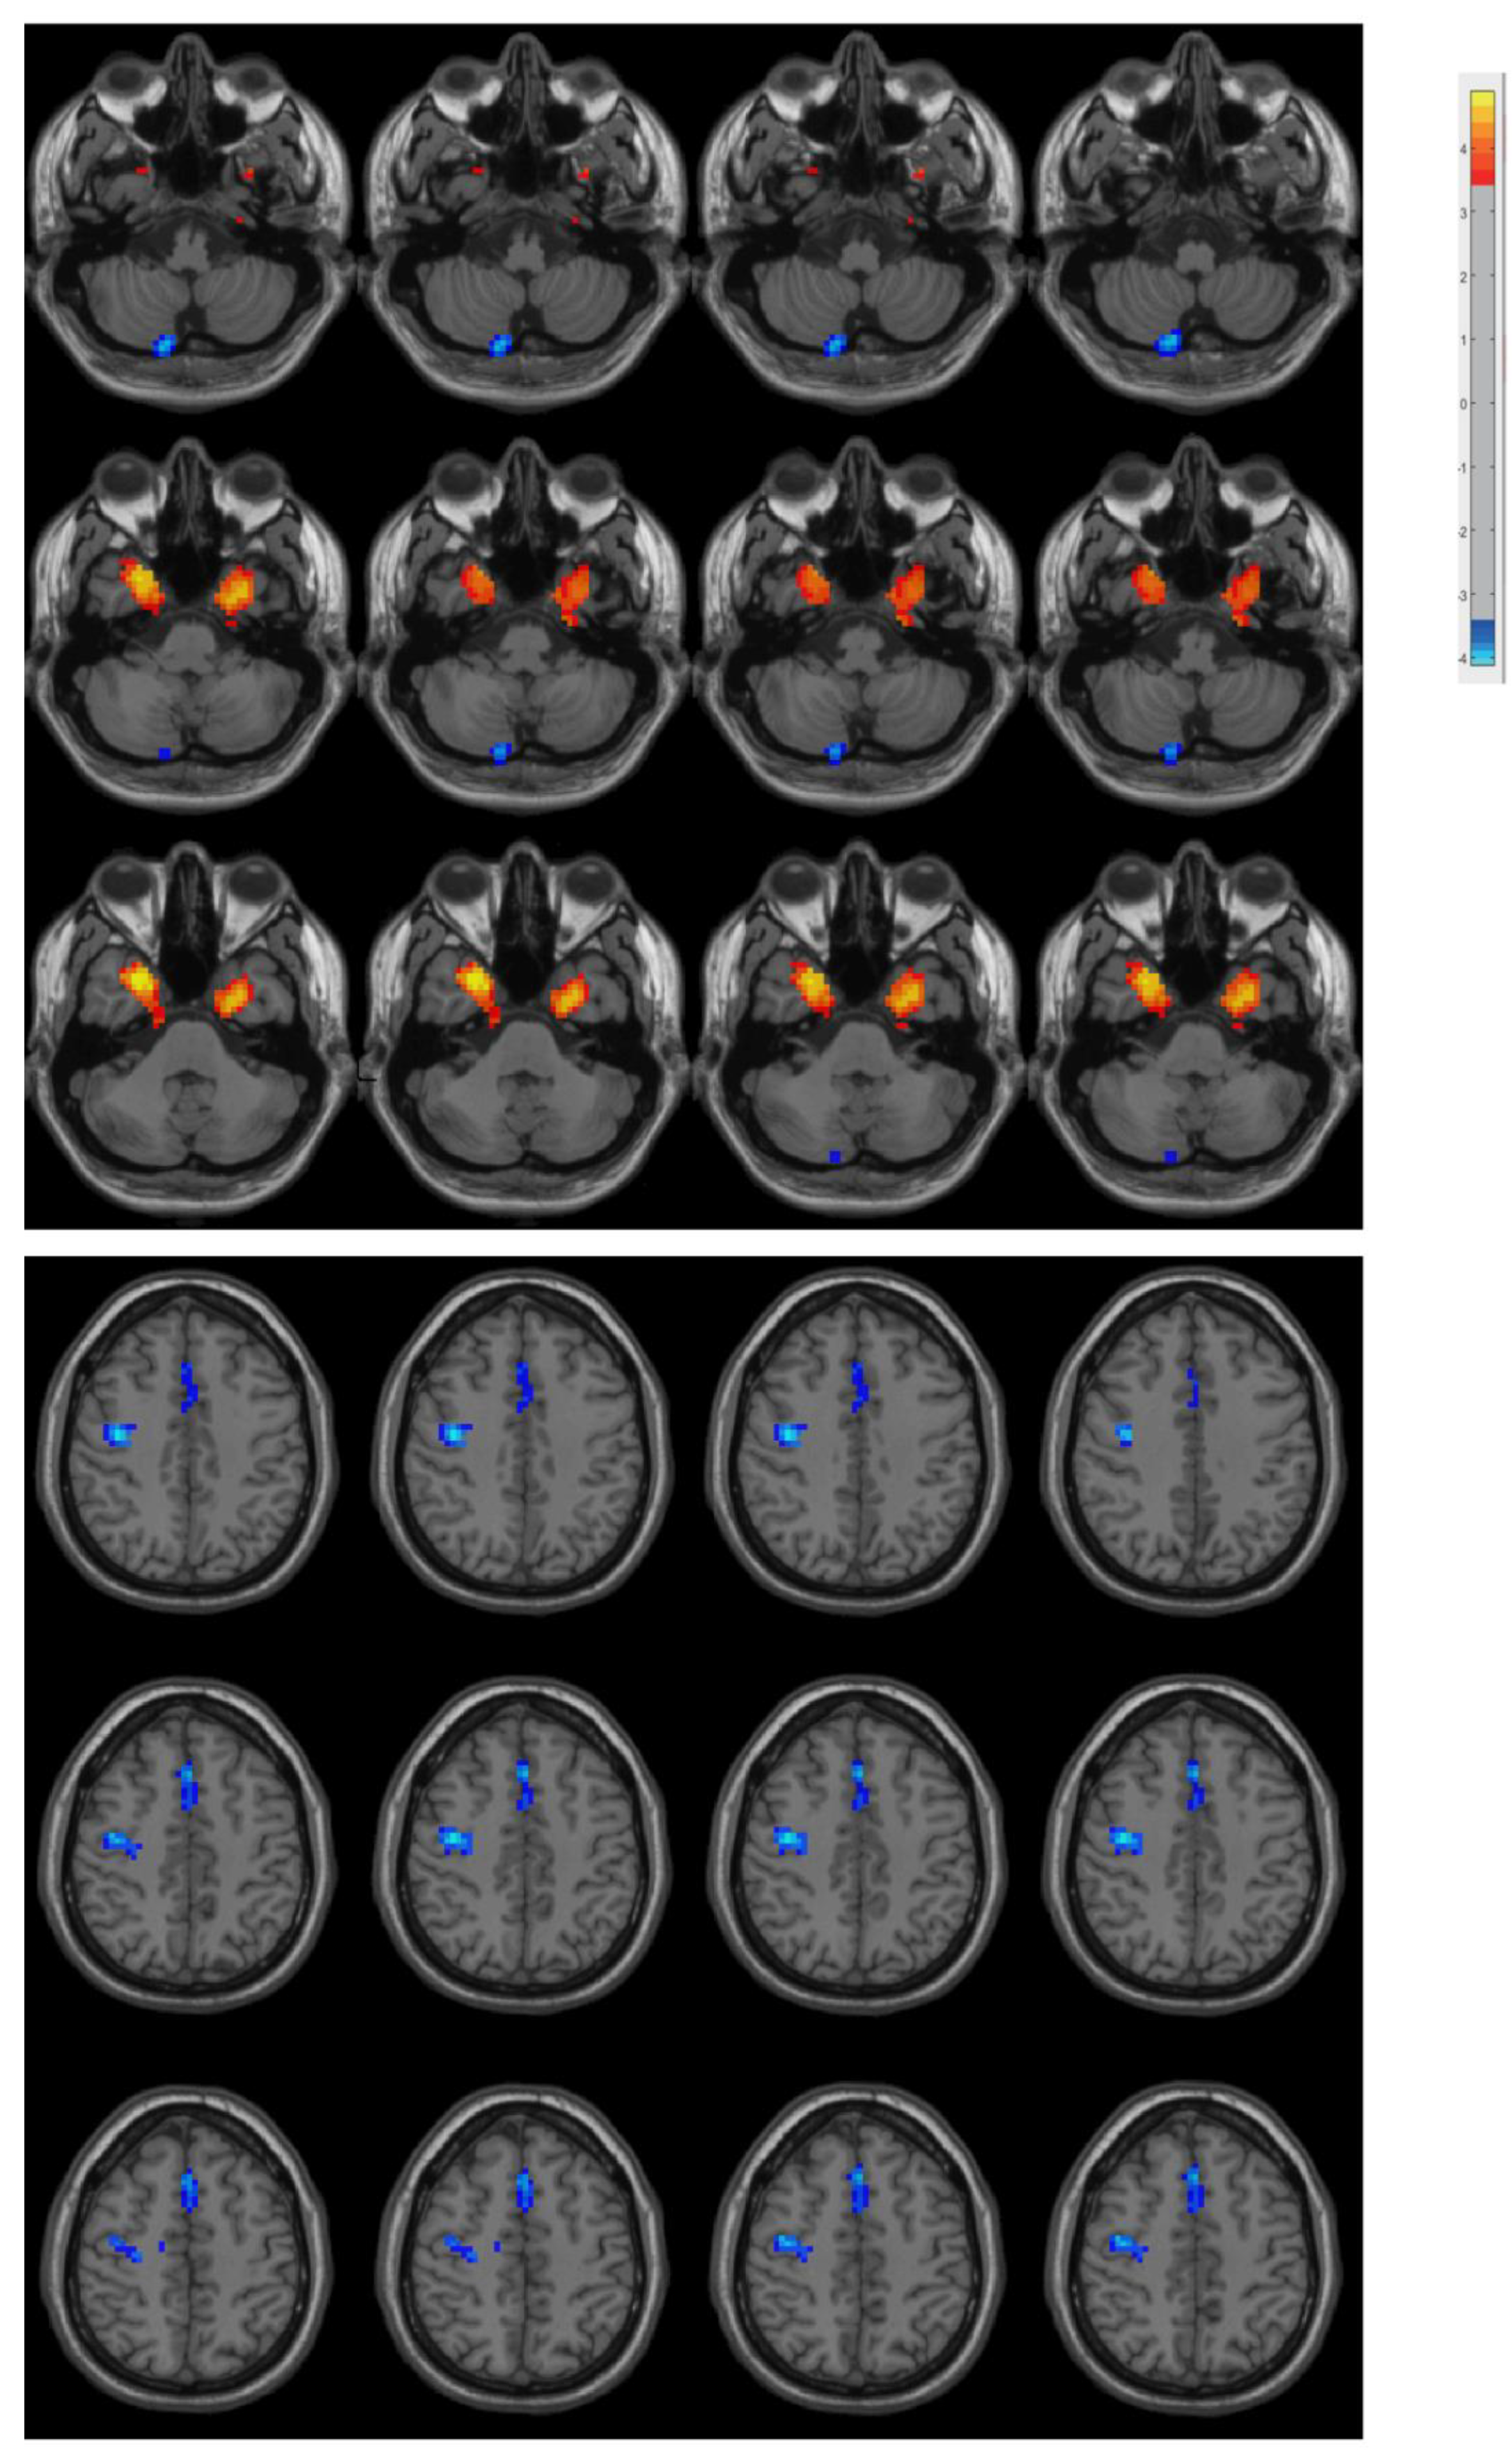

The PD patients had increased ReHo in the bilateral medial temporal lobe and decreased ReHo in the right posterior cerebellar lobe, right precentral gyrus, and supplementary motor area compared with the controls (Figure 1 and Table 2).

Figure 1.

Differences between groups in terms of ReHo. Compared with the controls, the PD patients had increased ReHo in the bilateral medial temporal lobe and decreased ReHo in the right posterior cerebellar lobe, right precentral gyrus, and supplementary motor area.

The present study found increased ReHo in the bilateral medial temporal lobe and decreased ReHo in the right posterior cerebellar lobe, right precentral gyrus, and medial frontal gyrus in PD patients compared with controls. These findings are consistent with previous reports [7,8,29,30,31,32,33,34]. The cerebellum, precentral gyrus, and supplementary motor area are closely associated with motor function, and the motor system is impaired in PD. Previous research has reported that ReHo is reduced in these areas among PD patients [7,8,29,31,32,33,34,35]. The medial temporal lobe is involved in Parkinson’s disease at Braak stage 4, closely following substantia nigra involvement, which leads to motor symptoms in Braak stage 3 [36]. Altered ReHo in this area has also been commonly reported to be abnormal in PD patients and is associated with neuropsychiatric symptoms, especially depression [31,34,35].